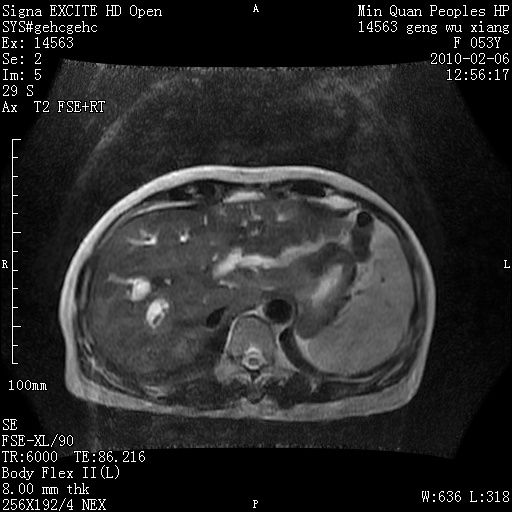

标题: MRI2762:胆道梗阻原因?

f,53y,全身黄染多日。

高位胆道梗阻 胆管癌可能性大

支持 高位胆道梗阻 胆管癌可能性大。